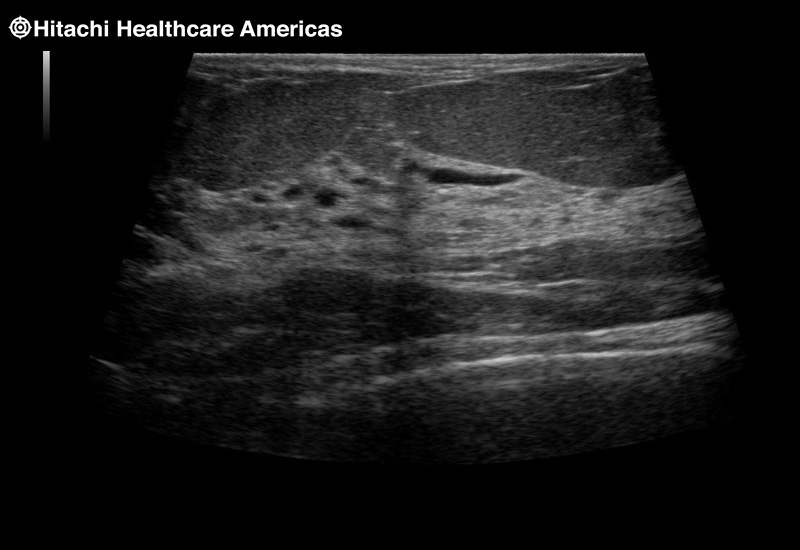

Fujifilm Healthcare's dedication to Surgeons provides outstanding ultrasound technology, professional support and the specialized tools necessary to best perform comprehensive real-time ultrasound imaging in Breast Surgery, General Surgery, Laparoscopic Surgery, Neurosurgery, Robotic Surgery and Surgical Oncology.

The Arietta 65 has many advanced and unique probes that fully cover the expanding range of procedures that benefit from ultrasound guidance.

The Arietta 65 has many advanced and unique probes that fully cover the expanding range of procedures that benefit from ultrasound guidance.